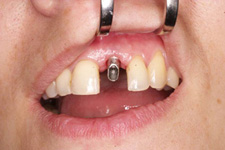

Klasickým příkladem a indikací pro použití implantátu je ztráta jednoho zubu (v tomto případě v předním – frontálním úseku) v jinak zdravém, nepoškozeném chrupu.

Nejčastější příčinou takové ztráty je sportovní nebo dopravní úraz.

Náhrada jednoho zubu pomocí implantátu je možná také v postranním úseku chrupu. Při ztrátě většího počtu zubů ve frontálním nebo postranním úseku může být mezer uzavřena větším počtem jednotlivých implantátů.

Při ošetření pomocí jednotlivých implantátů zůstávají sousední zuby neporušené – intaktní. Při klasickém ošetření pomocí můstků musejí být tyto zuby obroušeny!